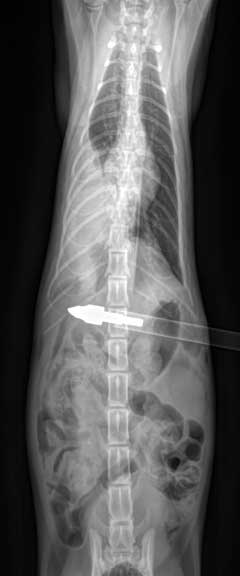

Pellet in the neck

Cat show with an arrow that penetrated the abdomen